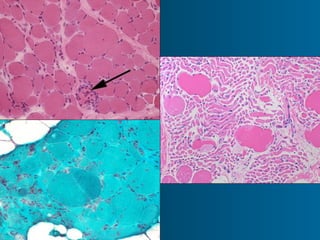

Muscle fiber types

• Type 1 (Slow Oxidative) 50%

• Type ll A (FOG) Red 35%

• Type ll B (Fast Glycosylated) White

15%